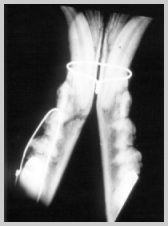

Intra-oral radiograph ventrodorsal mandible

- note lack of superimposition of maxillary structures